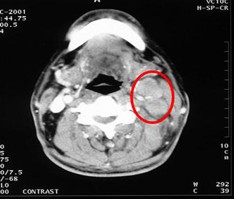

病例1 男,60歲,鼻咽癌Ⅲ 期,T2N2M0,治療前腫瘤充滿鼻咽腔和后鼻腔后緣,23.5cm2。治療方案:今又生瘤內(nèi)注射,1×1012VP/次/周,共6周,并聯(lián)合放療40Gy。治療后:腫瘤完全消退。治療前治療后 病例2 患者病情:…